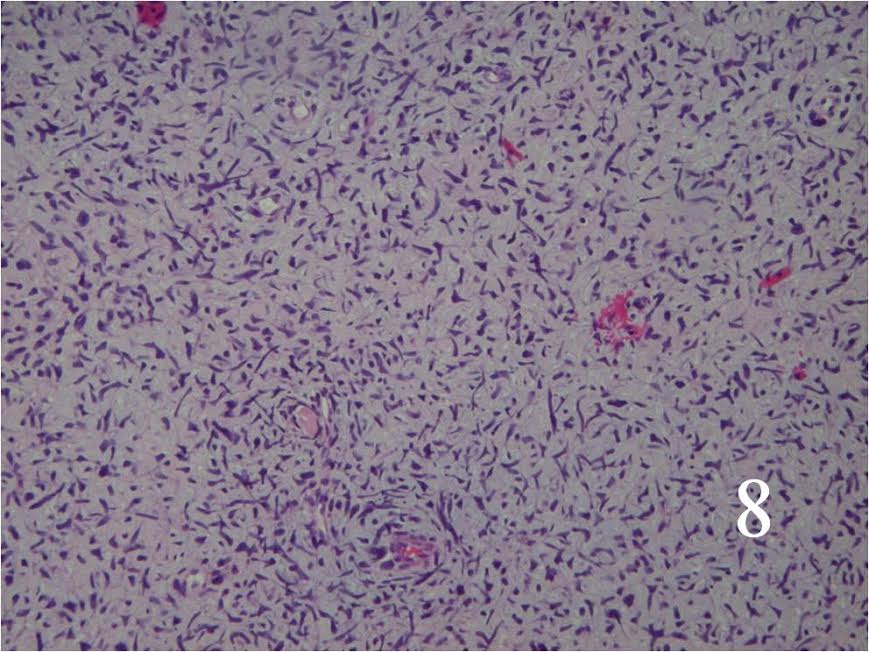

Microscopic

- Resembles fibrosarcomas

- Usually high grade features

- Spindle cells with markedly irregular contours (Fig. 7, 8)

- Nuclei are comma-shaped

- Cells are arranged in sweeping fascicles

Fig. 7 Low power and high power (Fig. 8) magnification on H&E staining shows a spindle cell neoplasm with high cellularity, abnormal mitotic features and nuclear atypia. The cells are arranged in a somewhat fascicular manner.